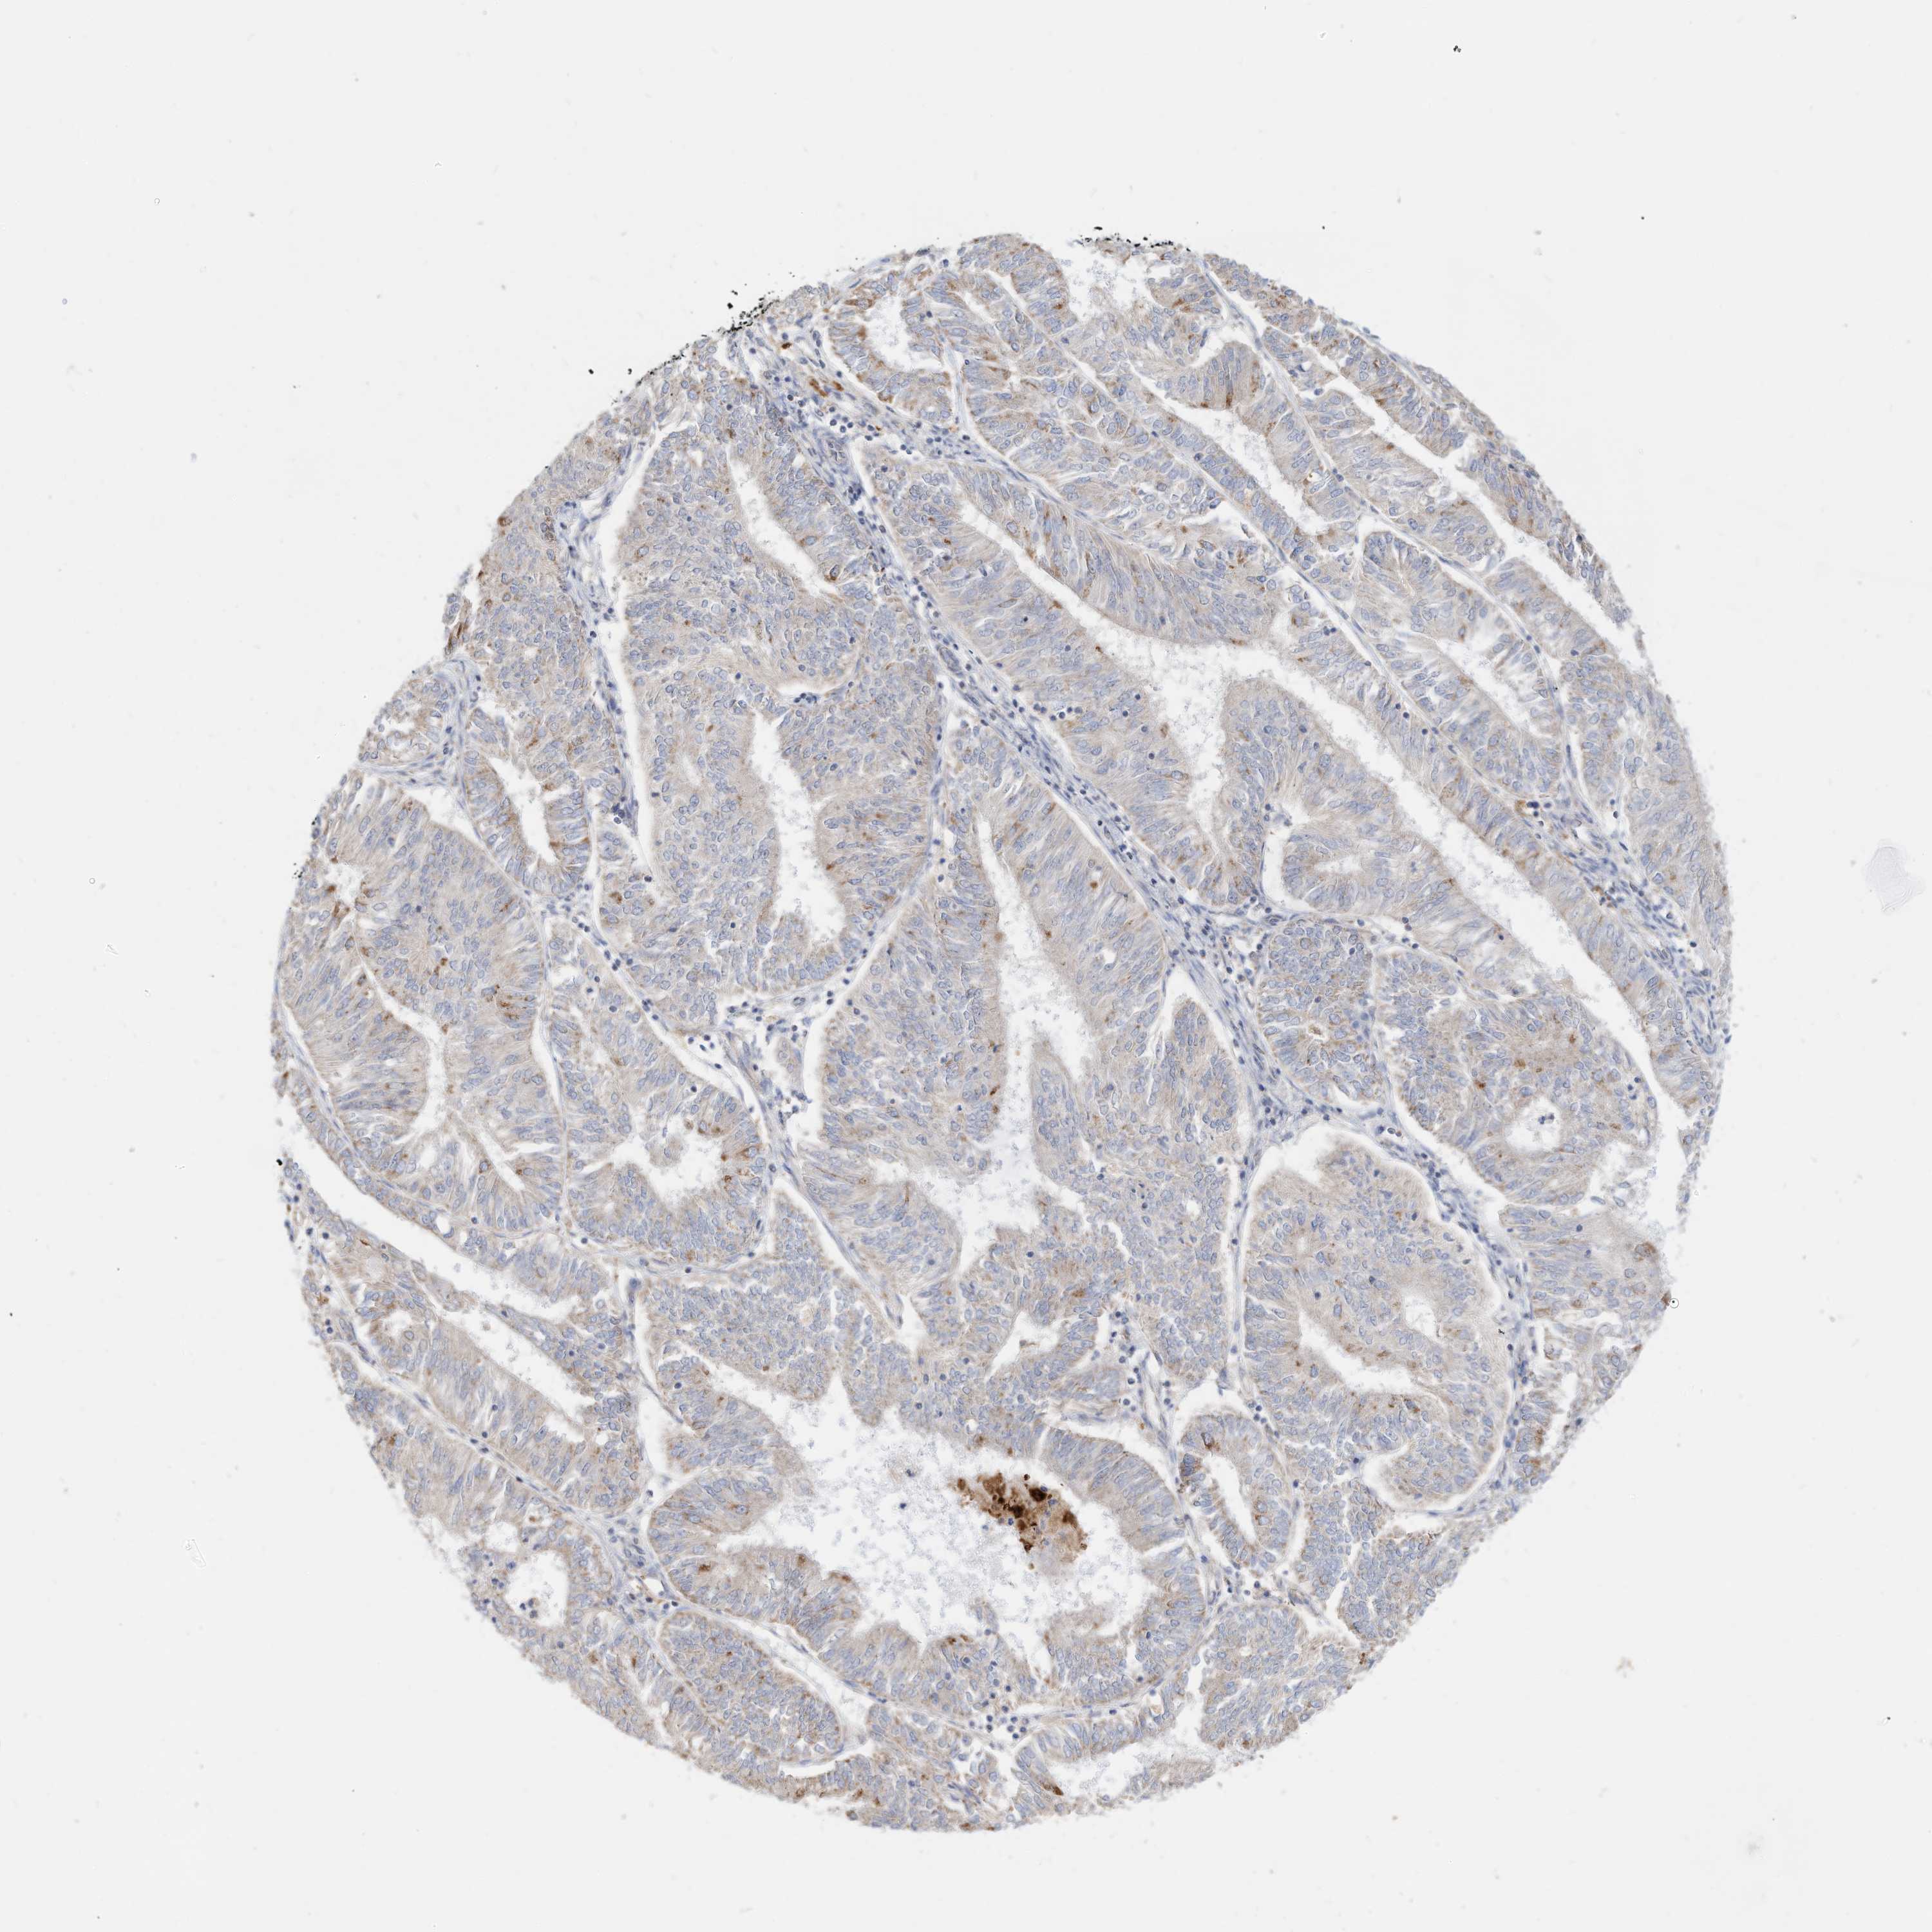

ENDOMETRIAL CANCER - Protein expressioni

A mouse-over function shows sample information and annotation data. Click on an image to view it in a full screen mode. Samples can be filtered based on level of antibody staining by selecting one or several of the following categories: high, medium, low and not detected. The assay and annotation is described here.

Note that samples used for immunohistochemistry by the Human Protein Atlas do not correspond to samples in the TCGA dataset.

Antibody stainingi

Antibody staining in the annotated cell types in the current human tissue is reported as not detected, low, medium, or high, based on conventional immunohistochemistry profiling in selected tissues. This score is based on the combination of the staining intensity and fraction of stained cells.

Each image is clickable and will lead to virtual microscopy that enables deeper exploration of all samples and also displays staining intensity scores, fraction scores and subcellular localization as well as patient and tissue information for each sample.

Antibody HPA030345

Staining

High

Medium

Low

Not detected

Intensity

Strong

Moderate

Weak

Negative

Quantity

>75%

75%-25%

<25%

None

Location

Nuclear

Cytoplasmic/membranous

Cytoplasmic/membranous,nuclear

Adenocarcinoma, NOS